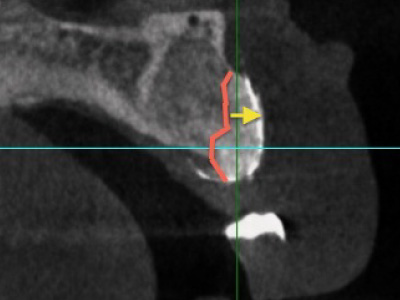

欧米人と比べてアジア人、特に日本人の上顎は下顎に比べて骨の量が少ない傾向にあります。さらに前歯は骨が薄く、女性は男性より薄いことが多いです。インプラントを支えるには、十分な骨の量が必要になってくるので、骨が少ないとインプラントがしっかりと生着しない事があります。

また、歯が無い期間が長いとだんだん骨が痩せていってしまうため、インプラント治療をする難易度が上がります。このように元々骨の量が少なく、インプラントを希望する患者さんの上の前歯の骨の量は少ない傾向にあるため、前歯のインプラントは難しいことが多いのです。

先述した通り、前歯は奥歯より骨が薄く、歯が抜けた箇所では骨吸収が起きるため、骨密度や骨量が不足しているケースが多いです。骨密度や骨量が不足している場合には「骨再生治療」が必要となり、インプラントを支えるための骨を増やす治療を行います。

インプラントは骨の中に入るようにできるだけ細いものを使用していますが、それでも骨造成は必要です。

インプラント周りに骨造成も実施しました。

前歯のインプラントは、とりわけ難易度が高い治療です。前歯のインプラント治療を難しくする大きな要因として、顎の骨が薄く骨の量が少ないことが挙げられます。このため、前歯のインプラント治療は特に高い技術を要します。